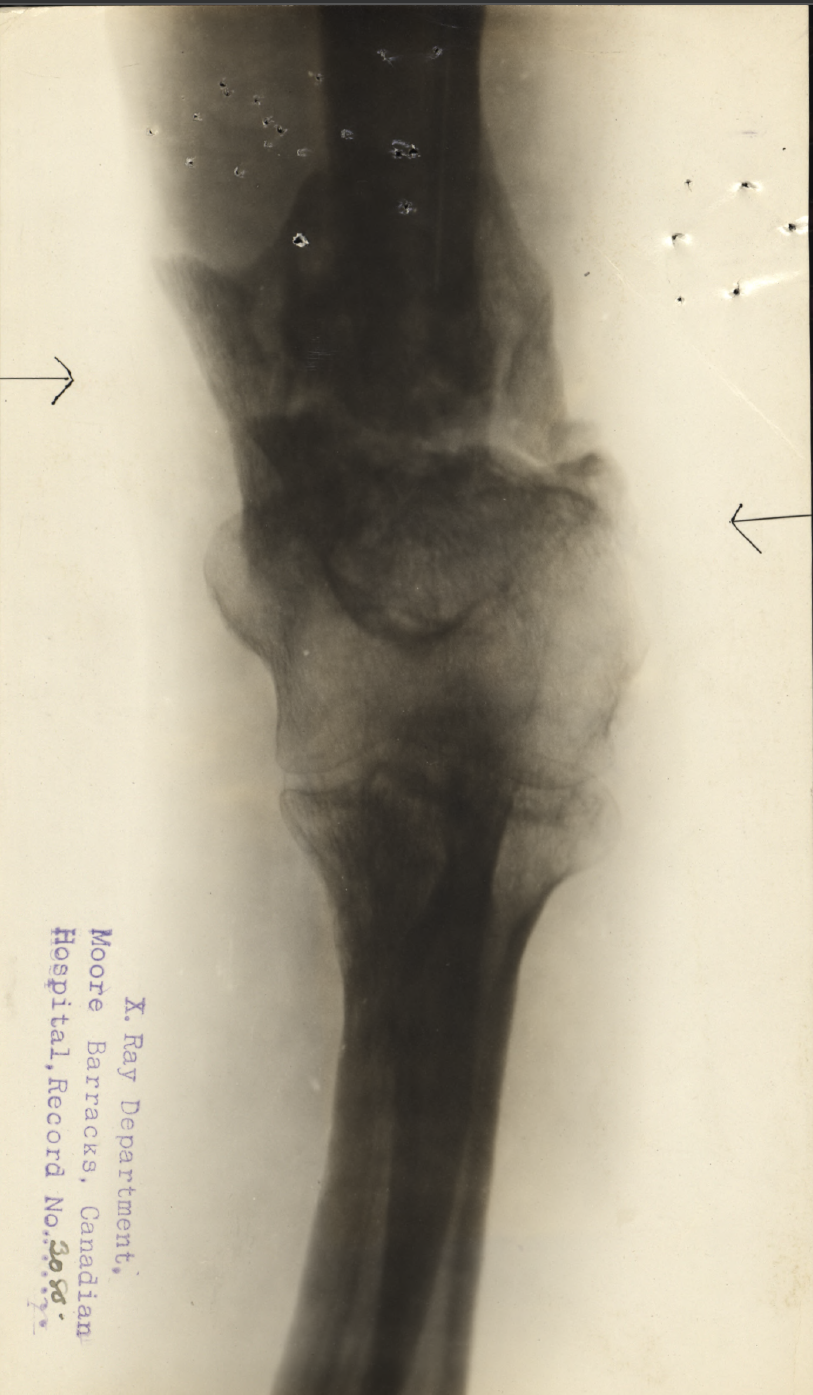

Family Search: When Private Herbert John Norman was born on 21 November 1888, in Charles, Devon, England, United Kingdom, his father, John Norman, was 28 and his mother, Mary Ann Barrow, was 31. He immigrated to Halifax, Nova Scotia, Canada in 1911. He registered for military service in 1915. In 1915, at the age of 27, his occupation is listed as teamster. He died on 7 August 1917, in Trafalgar, Halton, Ontario, Canada, at the age of 28, and was buried in Oakville, Halton, Ontario, Canada.